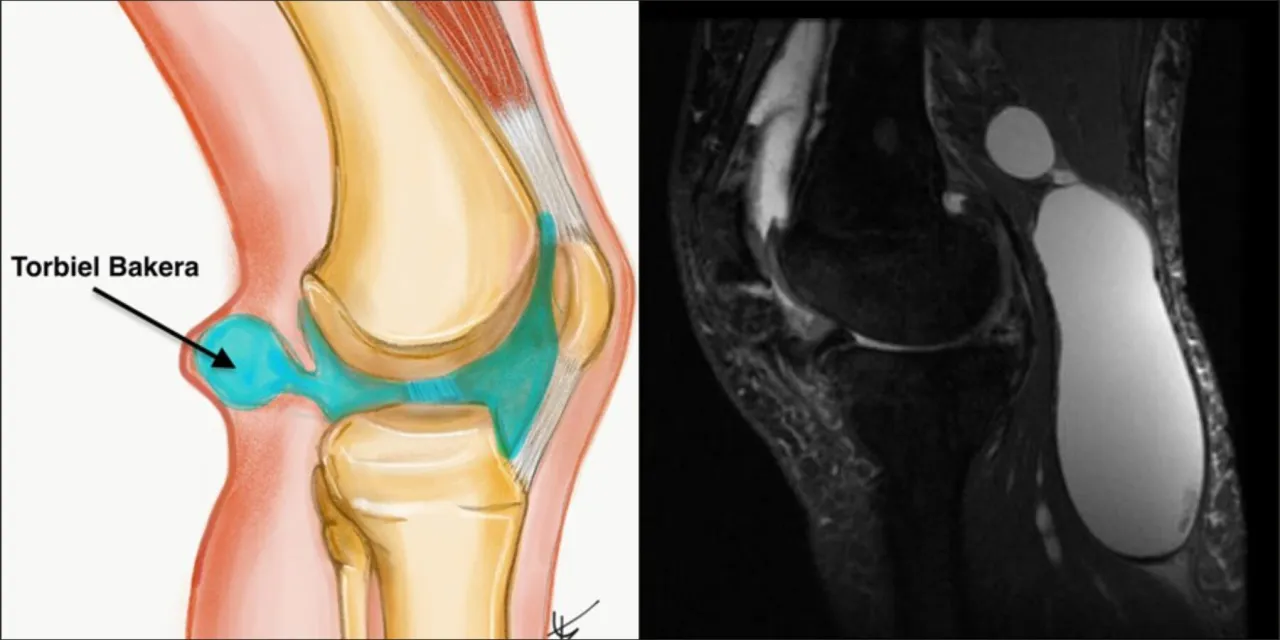

Torbiel Bakera to częsta dolegliwość kolana, która potrafi znacząco uprzykrzyć życie, powodując ból i dyskomfort w tylnej części stawu. Wiele osób, szukając ulgi, zastanawia się, jakie leki mogą pomóc. W tym artykule wyjaśnię, jakie farmakologiczne metody mogą przynieść ulgę w objawach, ale jednocześnie podkreślę, dlaczego kluczowe jest leczenie pierwotnej przyczyny problemu. Zapraszam do lektury, aby zrozumieć kompleksowe podejście do terapii tej dolegliwości.

Kiedy pojawia się torbiel Bakera, naturalne jest, że szukamy szybkiej ulgi. Leczenie farmakologiczne tej dolegliwości koncentruje się przede wszystkim na łagodzeniu objawów, takich jak ból i stan zapalny, które często towarzyszą powiększeniu się torbieli. Należy jednak pamiętać, że leki rzadko eliminują torbiel całkowicie, jeśli nie zostanie usunięta jej pierwotna przyczyna. To kluczowa informacja, którą zawsze staram się przekazać moim pacjentom.

Z mojego doświadczenia wynika, że torbiel Bakera jest zazwyczaj wtórnym objawem innego, głębiej zakorzenionego problemu w stawie kolanowym. Może to być uszkodzenie łąkotki, choroba zwyrodnieniowa, a nawet reumatoidalne zapalenie stawów (RZS). Leki, choć niezwykle skuteczne w redukcji objawów i poprawie komfortu życia, nie są w stanie usunąć źródła nadprodukcji płynu stawowego. To właśnie ten nadmiar płynu, uwięziony w kaletce maziowej, tworzy torbiel. Dlatego tak ważne jest, aby nie poprzestawać na leczeniu objawowym, ale dążyć do postawienia precyzyjnej diagnozy i zajęcia się pierwotną przyczyną.Rola farmakoterapii: leczenie objawów, a nie przyczyny

Uważam torbiel Bakera za swoisty sygnał alarmowy, który wysyła nasze kolano. Jest to często objaw innych, poważniejszych problemów w stawie. Najczęstsze przyczyny to uszkodzenia łąkotki, na przykład pęknięcia, które prowadzą do niestabilności i stanu zapalnego. Inną bardzo powszechną przyczyną jest choroba zwyrodnieniowa stawów (osteoartroza), gdzie chrząstka stawowa ulega zniszczeniu, generując stan zapalny i nadmierną produkcję płynu stawowego. Inne urazy wewnątrzstawowe również mogą prowadzić do tego stanu. We wszystkich tych przypadkach, uszkodzone struktury powodują nadmierną produkcję płynu stawowego, który, szukając ujścia, gromadzi się w torbieli.